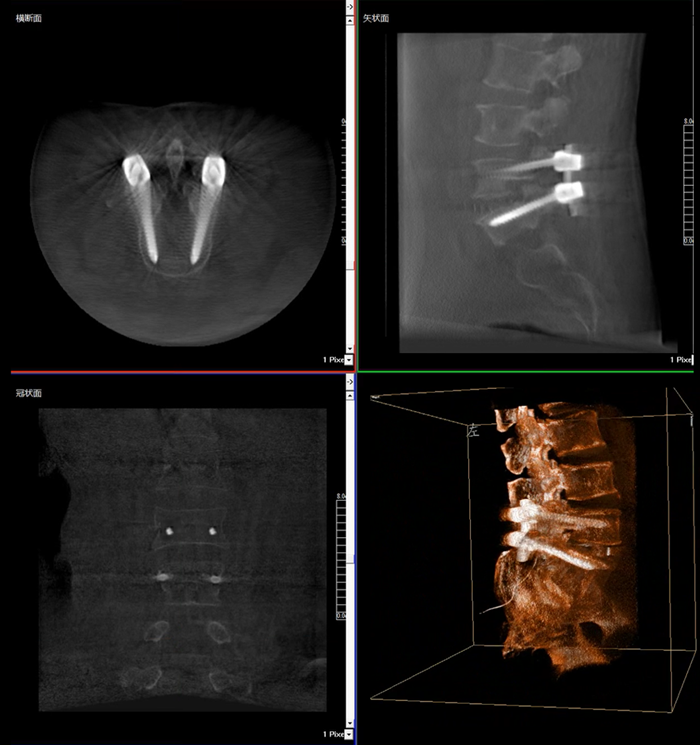

移動(dòng)式三維C形臂,又稱骨科三維C臂,就是將傳統(tǒng)二維與“類CT模式”相結(jié)合的升級(jí)版C形臂,能在術(shù)中快速地生成橫斷面、矢狀面、冠狀面斷層圖像和三維立體圖像。通過(guò)不同方位的斷層圖像,能夠更清晰、完整地顯示椎體及其附件的解剖學(xué)結(jié)果,直觀地分析病變與周圍組織的立體空間關(guān)系,三維斷層成像能夠使手術(shù)模擬和手術(shù)方案的制定更加準(zhǔn)確。

而三維影像的MPR圖像組可以通過(guò)不同平面的切分,使成像區(qū)內(nèi)更豐富的信息得以呈現(xiàn)。尤其是二維影像無(wú)法涉及的橫斷面,提供了另一個(gè)空間維度的信息量。

在MPR圖像中,冠狀面、矢狀面和橫斷面的信息大大提高了醫(yī)生對(duì)于病灶區(qū)以及手術(shù)效果的判定。